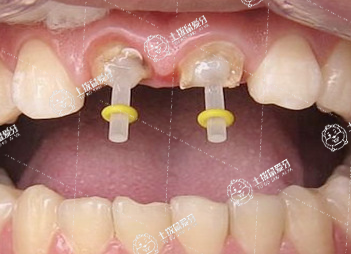

根管治療是一個相對比較復(fù)雜的治療過程,一般用來治療牙髓炎或者根尖周病變的牙齒。根管治療大概分為開髓、根管測長及預(yù)備、根管充填三步,開髓的目的是暴露根管口,測長及預(yù)備是為了清理感染物質(zhì),根管充填是為了嚴密封閉牙齒的根管系統(tǒng)。